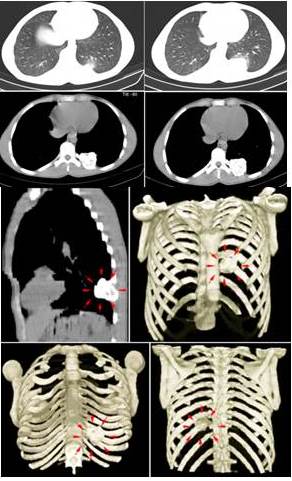

En la TC de tórax con reconstrucción en 3D, se evidenció imagen hiperdensa con áreas hipodensas en su interior, redondeada de bordes bien definidos micro-lobulados que mide 4,3 cm x 4,3 cm a nivel del 1/3 proximal del décimo (10o) arco costal posterior izquierdo con protrusión de dicha lesión hacia el parénquima pulmonar y partes blandas dorsal compatible con lesión neoplásica benigna. Resto del plano óseo y blando sin evidencia de lesiones (Figura 2).

Se realiza survey óseo de cuerpo entero y estática de tórax, el rastreo corporal mostraba lesión ocupante de espacio con aumento importante en la actividad de concentración del radio-trazador proyectado en hemitórax izquierdo a la altura del décimo arco costal posterior izquierdo con importante actividad expansiva y deformante (Figura 3).